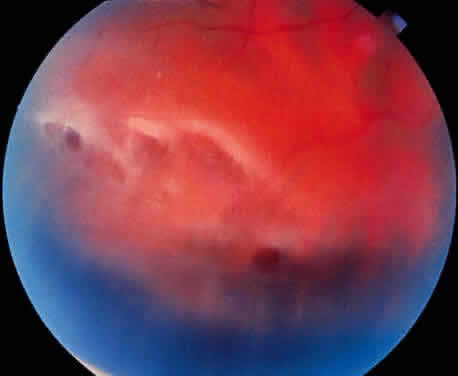

Fig. 21. Clinical appearance of reticulardegenerative retinoschisis: diagram of

involved area and photographs of ocular fundus showing optic disc, macula, and

posterior portion of the schisis. These illustrate outer layer

retinal breaks, adjacent retinal pigment epithelium abnormality, and

a lo-calized nonrhegmatogenous retinal detach-ment. Fig. 21. Clinical appearance of reticulardegenerative retinoschisis: diagram of

involved area and photographs of ocular fundus showing optic disc, macula, and

posterior portion of the schisis. These illustrate outer layer

retinal breaks, adjacent retinal pigment epithelium abnormality, and

a lo-calized nonrhegmatogenous retinal detach-ment.